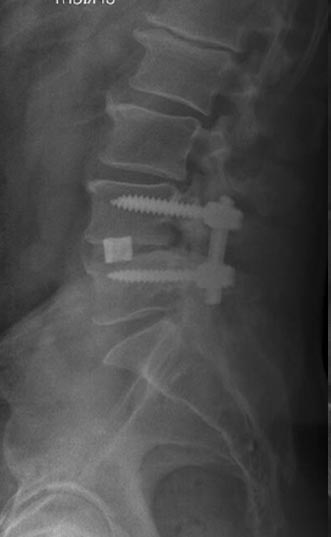

44 year old man with severe low back pain with intermittent radiation of the pain down the right leg. After undergoing conservative treatment, continued to have debilitating pain. MRI revealed a right paracentral disc herniation but CT scan revealed a unilateral pars fracture. After debating on microdiscectomy vs fusion, patient elected to undergo lumbar fusion. 4 months postop patient returned to surfing again. 9 months postop patient wrote “My recovery continues to do very well and we just got back from 8 days camping which including mountain biking, hiking, and a lot of work. Surfing almost every day and life is good…you have helped get my life and my families life back to normal.”

After procedure.